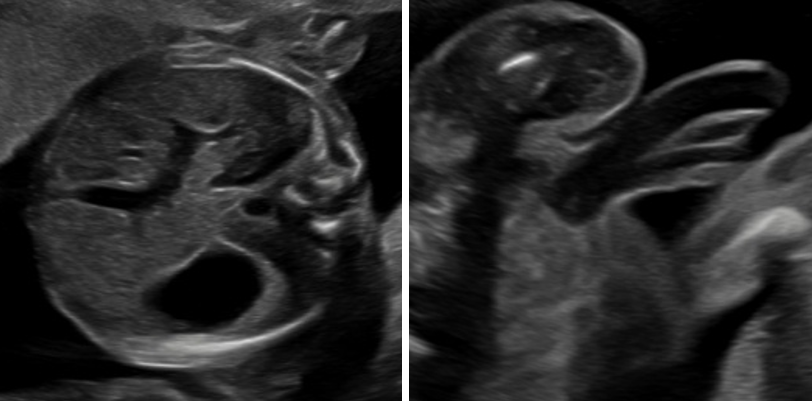

„Feindiagnostik“: 20-24 SSW

Wir schauen Ihr Kind im Ultraschall detailliert von Kopf bis Fuß an. Mit Fortschreiten der Schwangerschaft liegt der Fokus hier besonders auf der Entwicklung von Herz und Kopf Ihres Kindes. So können wir Besonderheiten frühzeitig erkennen, die Schwangerschaft optimal begleiten und die Geburt bestmöglich vorbereiten. In manchen Fällen ist eine Behandlung bereits während der Schwangerschaft möglich.

Je nach Fragestellung kann diese Untersuchung auch zu einem deutlich früheren oder späteren Zeitounkt sinnvoll sein.